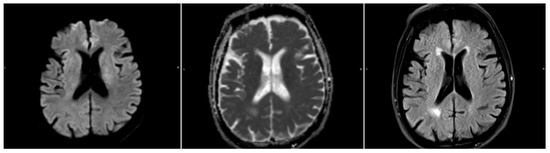

Figure 2. A sample where the automatic DWI segmentation has missed the stroke, located next to the ventricle. From left to right: DWI (b1000), ADC, and FLAIR.

3.2. DWI/FLAIR Mismatch Agreement

We ran the automated DWI segmentation as well as our FLAIR segmentation method on the Wake-up dataset. Out of the 51 cases, 4 cases were excluded due to the automatic DWI segmentation missing the stroke completely (Figure 2). A quantitative comparison between these patients with missed DWI segmentation and the rest of the cohort showed that the missed lesions all had subtle DWI lesions in regard to intensity. Furthermore, 1 case was excluded due to the stroke being located across the mirroring plane, with more than 20 % of the contralateral information being from the stroke itself (Figure 3).